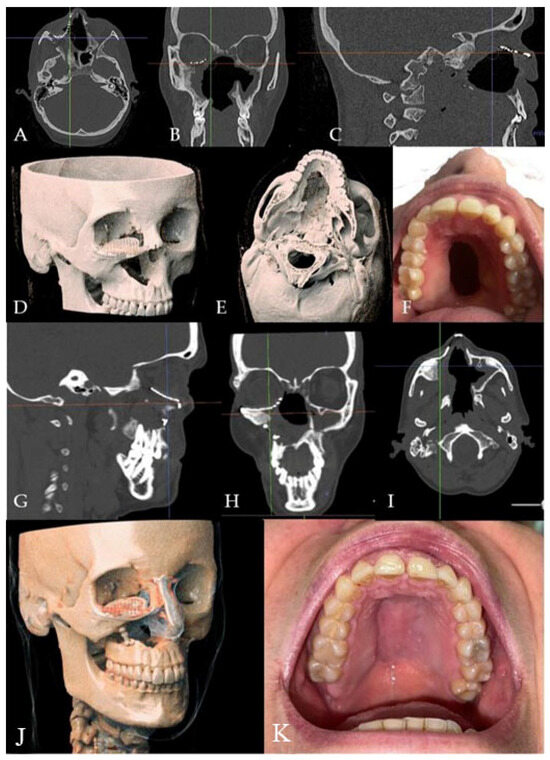

2.2. Case 2

A 52-year-old male patient came to our attention in 2017, presenting with a palatal/oro-nasal fistula measuring 3.5 cm in diameter along the major axis, with atrophic soft tissues surrounding the lesion (Ia according to the Okay et al. classification [14]). The patient had already been treated in 2015 in another center using a palatal local flap with no success and was then treated with an obturator. At the clinical and radiographic examination (Figure 4), a wide oro-nasal communication with exposure of the nasal cavity and septum was observed, leading to speech disturbances, rhinolalia, and eating difficulties.

Figure 4. (A) Clinical presentation of the oro-nasal communication. In inset A, it is possible to appreciate the visibility of the nasal septum. (B,C) Radiographic and 3D reconstruction using InVivo6® and Anatomage Table EDU vers.8® (Santa Clara, CA, USA) software. DICOM files were imported in InVivo6® (Santa Clara, CA, USA) software to obtain the axial, cross, and panorex sections. Afterwards, the DICOM files were imported into Anatomage Table EDU vers.8® (Santa Clara, CA, USA) to obtain the 3D rendering.

The patient attended follow-up appointments at 1 week, 1 month, 6 months, and one year, with complete resolution of the fistula. The patient showed an improved ability to speak and no issues with eating, as confirmed by clinical and radiographic controls (Figure 6).

Figure 6. (A) One-year clinical follow-up. (B) Radiological one-year follow-up.